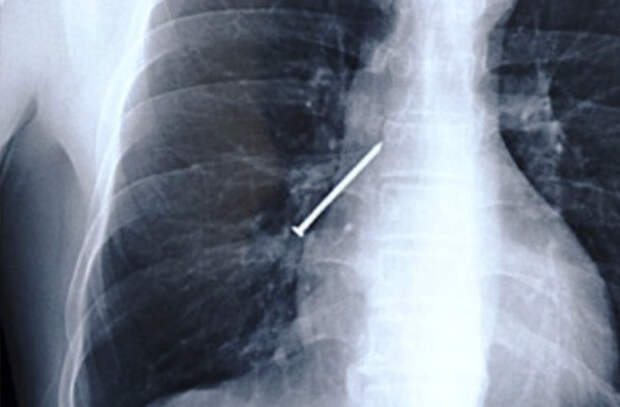

Рентген, на котором виден катетер, введенный доктором в свое тело

Вернер Форсман рассматривает рентгеновские снимки своего тела с катетером

Здесь и далее: инородные предметы внутри человека, рентген